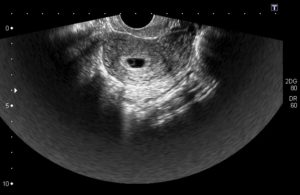

Для установления наличия и срока беременности врач проводит трансвагинальное УЗИ. Этот доступ позволяет лучше рассмотреть полость матки, достовернее измерить размер и оценить структуру плодного яйца.

На раннем сроке с 4 по 6 недели срок беременности устанавливают по диаметру плодного яйца. Для этого врач проводит измерение диаметра плодного яйца по его внутреннему контуру в 3 взаимоперпендикулярных плоскостях.

Трансвагинальное УЗИ покажет плодное яйцо в полости матки, когда наступят 4,5 – 5,0 недель беременности. Стоит отметить, что врачи считают продолжительность беременности с первого дня крайних месячных.

В ранние сроки, как и при стандартном гинекологическом УЗИ, измеряют размеры матки, яичников, шейки матки.

Специфическими показатели, которые обязательно определяются в первом триместре являются:

• диаметр плодного яйца (с 4 по 6 неделю);

• копчико – теменной размер (с 7 по 14 неделю);

• диаметр желточного мешка;

• размер желтого тела в яичнике.